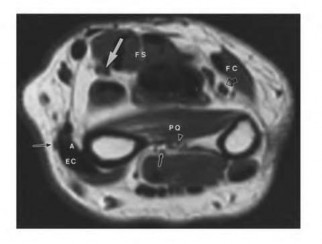

The clinical and radiographic description is classic for Ewing sarcoma. The characteristic cytogenetic abnormality is a balanced translocation t(11;22)(q24;q12), which fuses the EWS gene on chromosome 22 with the FLI1 gene on chromosome 11. This is seen in approximately 85-90% of Ewing sarcomas. t(9;22) is the Philadelphia chromosome (CML), t(X;18) is seen in synovial sarcoma, t(2;13) in alveolar rhabdomyosarcoma, and t(12;16) in myxoid liposarcoma.